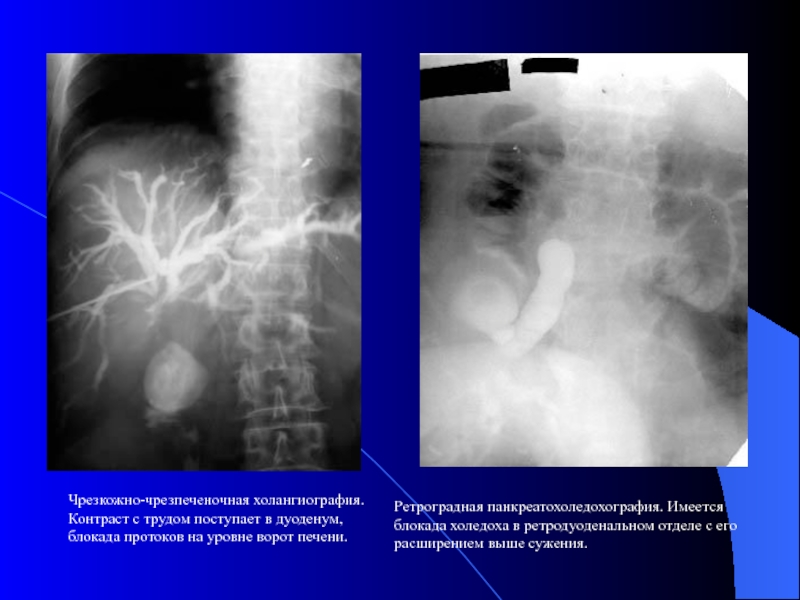

Слайд 15

Ретроградная панкреатохоледохография. Имеется блокада холедоха в ретродуоденальном отделе с его расширением

выше сужения.